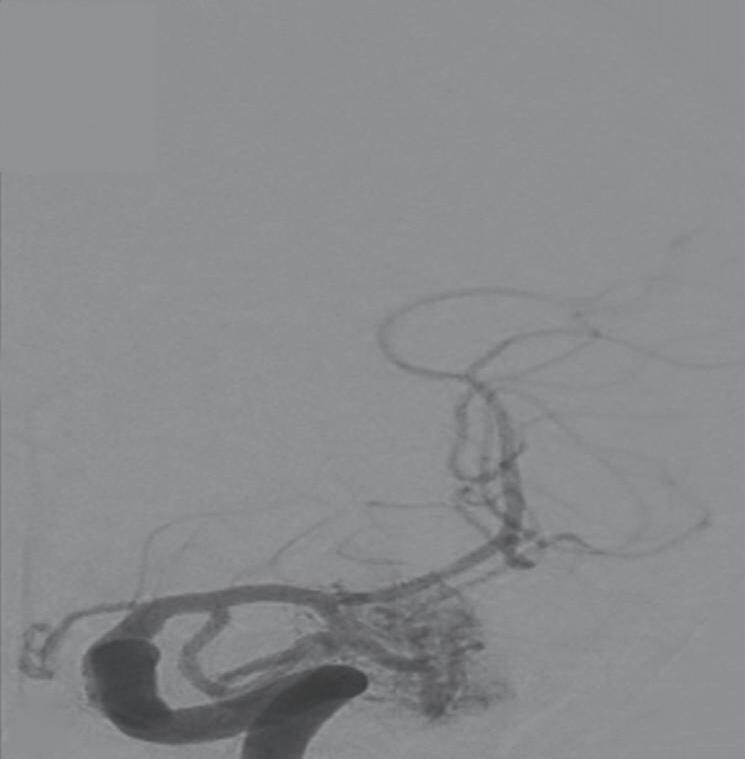

Fig. 1-8. (a-c) RNM T1 com contraste, cortes sagital (a), coronal (b) e axial (c) demonstrando MAV não rota com nidus localizado no lobo occipital à esquerda (setas longas). (d) Arteriografia digital cerebral com injeção de contraste via carótida direita (AP) mostrando a contribuição da carótida direita na irrigação da MAV contralateral. (e,f) Com injeção de contraste via carótida esquerda, em Perfil e AP respectivamente, observa-se nidus compacto nutrido por ramos da artéria cerebral média à esquerda e a veia de drenagem precoce se dirigindo para o seio sagital superior. Projeções em AP (g) e em perfil (h) demonstrando a contribuição do sistema vertebrobasilar por meio de ramos distais da artéria cerebral posterior à esquerda e drenagem para os seios sagital superior e sigmoide à esquerda (setas curtas).